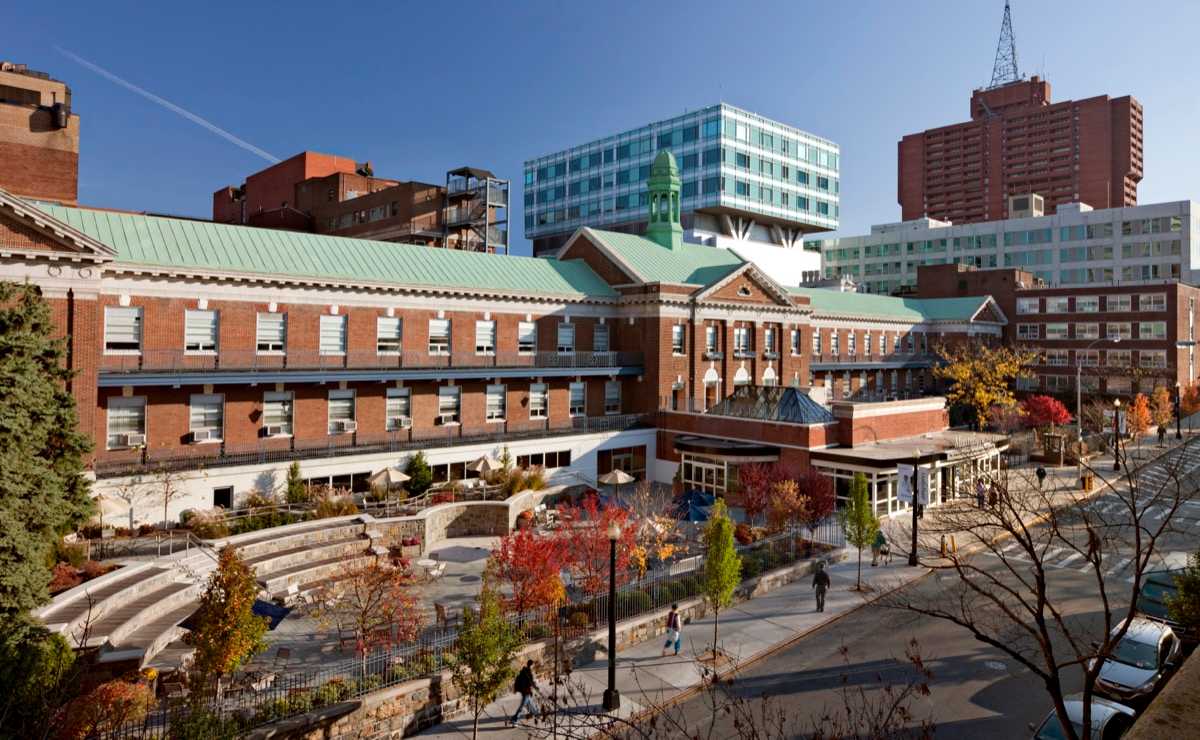

An academic hospital adjacent to our Albert Einstein College of Medicine

Jack D. Weiler Hospital is a 421-bed hospital located in the Pelham Parkway/Morris Park section of the Bronx. Weiler, which is positioned within the Einstein Campus, benefits from its close proximity to Albert Einstein College of Medicine and the Montefiore Einstein Center for Cancer Care. Residents rotate through anatomic pathology (typically gynecologic and breast pathology), laboratory management, clinical chemistry and transfusion medicine.